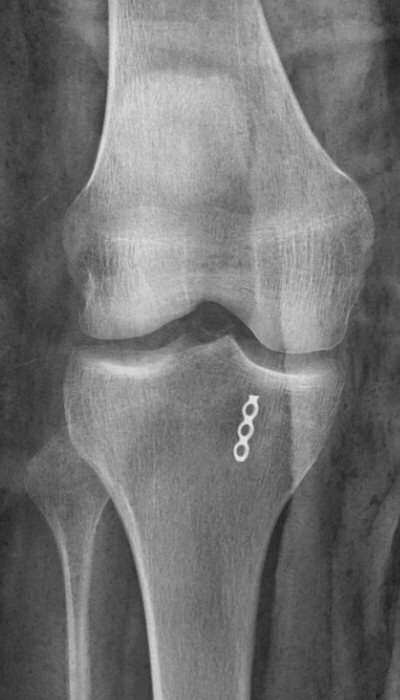

Första bilden eminentiafraktur typ III (och segondfraktur), andra bilden efter operation med sutur.